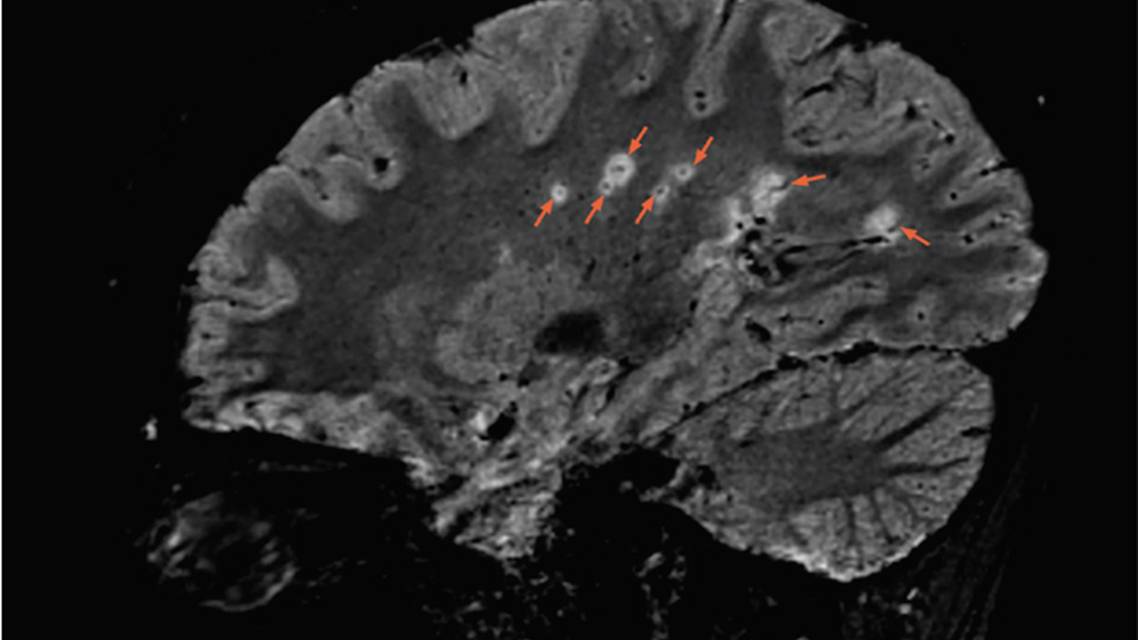

A sagittal 3T FLAIR* brain MRI shows multiple lesions with the central vein sign (orange arrows), appearing as hypointense dots or lines, located centrally within the lesion, depending on the blood vessel orientation. The FLAIR* technique was developed by Daniel S. Reich, MD, PhD and colleagues as described in Sati P, et al. Radiology. 2012;265(3):926-932. Image contributed by Daniel S. Reich, MD, PhD.